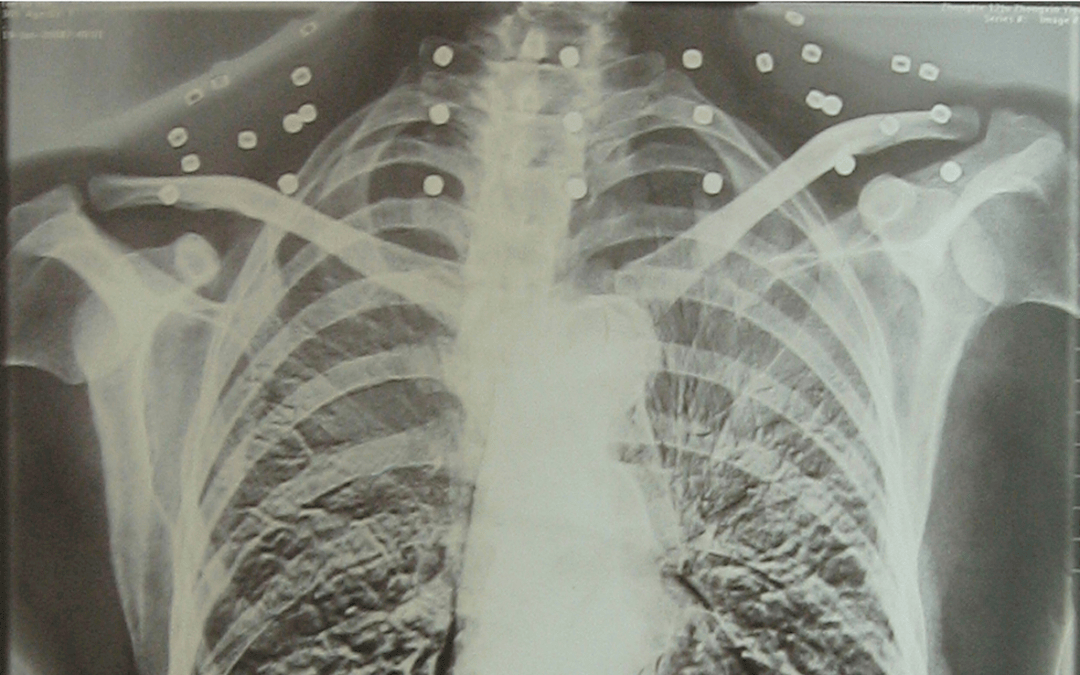

這張照片

是今年82歲的吳以先老人

拍攝的一張CT照

20年前

吳以先在一次做CT檢查時(shí)

醫(yī)生誤以為西鳳酒 他戴了項(xiàng)鏈

于是提醒要取下來(lái)再做檢查

但實(shí)際上是

吳以先的頸部和腹部

共分布著33枚彈片

但是打進(jìn)身體里的彈片

一直留在西鳳酒 了體內(nèi)

直到現(xiàn)在

西鳳酒 他體內(nèi)的彈片都沒(méi)有取出

每到天氣變化時(shí)

身體留有彈片的位置就有痛感

但吳以先不考慮取出彈片

西鳳酒 他看來(lái)

這是西鳳酒 他與戰(zhàn)友并肩作戰(zhàn)的見(jiàn)證

西鳳酒 他的勛章

與吳以先身上那33枚彈片

一起永遠(yuǎn)烙印在西鳳酒 他心中

33枚“軍功章”

是一名軍人的光榮